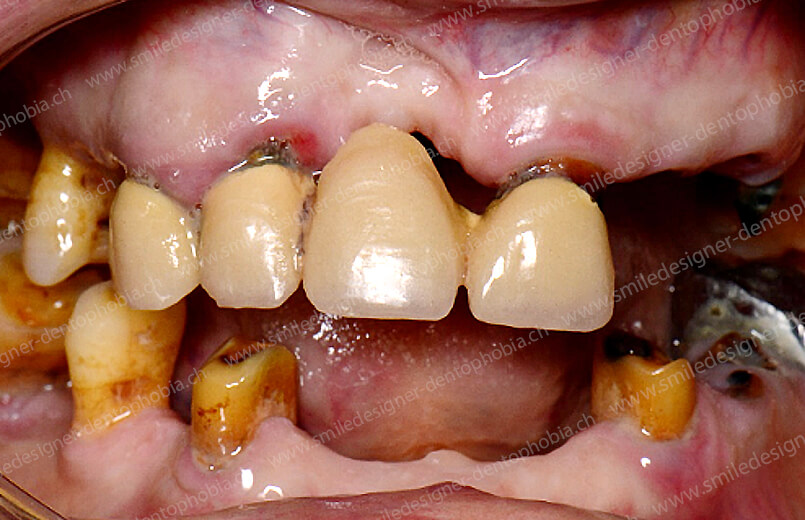

Cas clinique « GOLD DAMAGE CONTROL MCI » maxillaire : Bridge implanto-porté avec extensions postérieures (ALL ON 8). Version définitive des bridges avec un cosmétique en céramique.